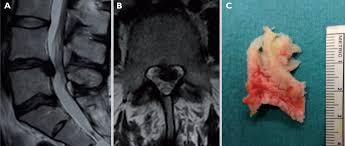

Hernia de disc lombara este o deplasare a discului intervertebral. Infection which turned my l5 and s1 vertebrae into cottage cheese. the surgery took four surgeons eight hours. Hernia de disc apare când inelul fibros crapă, iar nucleul pulpos alunecă și presează nervii, cauzând durere severă și constantă.